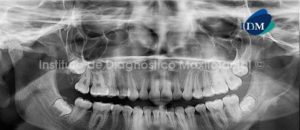

014 – Neurofibromatosis

Paciente de sexo femenino y de 21 años de edad es referida al Instituto de Diagnóstico Maxilofacial para la evaluación de su estado dental y periodontal.